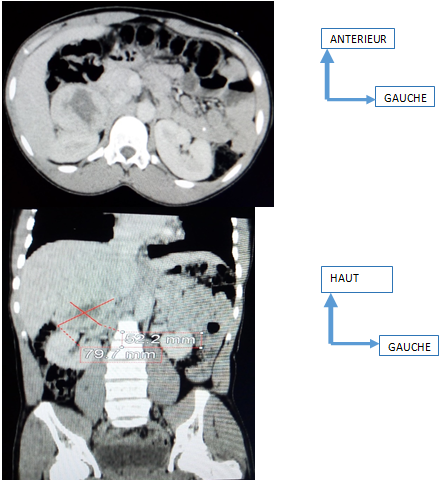

Abdominal ultrasound performed using the 3.5 Mhz convex probe showed a well-limited right adrenal mass, with regular contours, heterogeneous echostructure 79 mm long axis, with a necrotic center, with hyper vascularization on color Doppler of the fleshy portion. It was in close contact with the right upper renal pole. The abdominal CT examination (Figure 1) carried out following the ultrasound also shows the right adrenal mass with a necrotic center measuring 79.7 x 52.2 mm, the spontaneous density of the tissue portion of which is measured at 35 UH, the density at portal time at 75 HU and density at 10 min after intravenous injection of contrast product at 52 HU. Thus the relative and absolute “Wash out” is evaluated at 6% and 39%. There was no intraperitoneal or extraperitoneal fluid effusion, no infiltration of peritoneal fat and no lumbo-aortic, coelio-mesenteric or pelvic ADP.

Figure 1 Abdominal CT scan with portal phase image acquisition, axial section and coronal reconstruction in parenchymal window showing a necrotic right adrenal mass of 79 x 67 x 53mm.